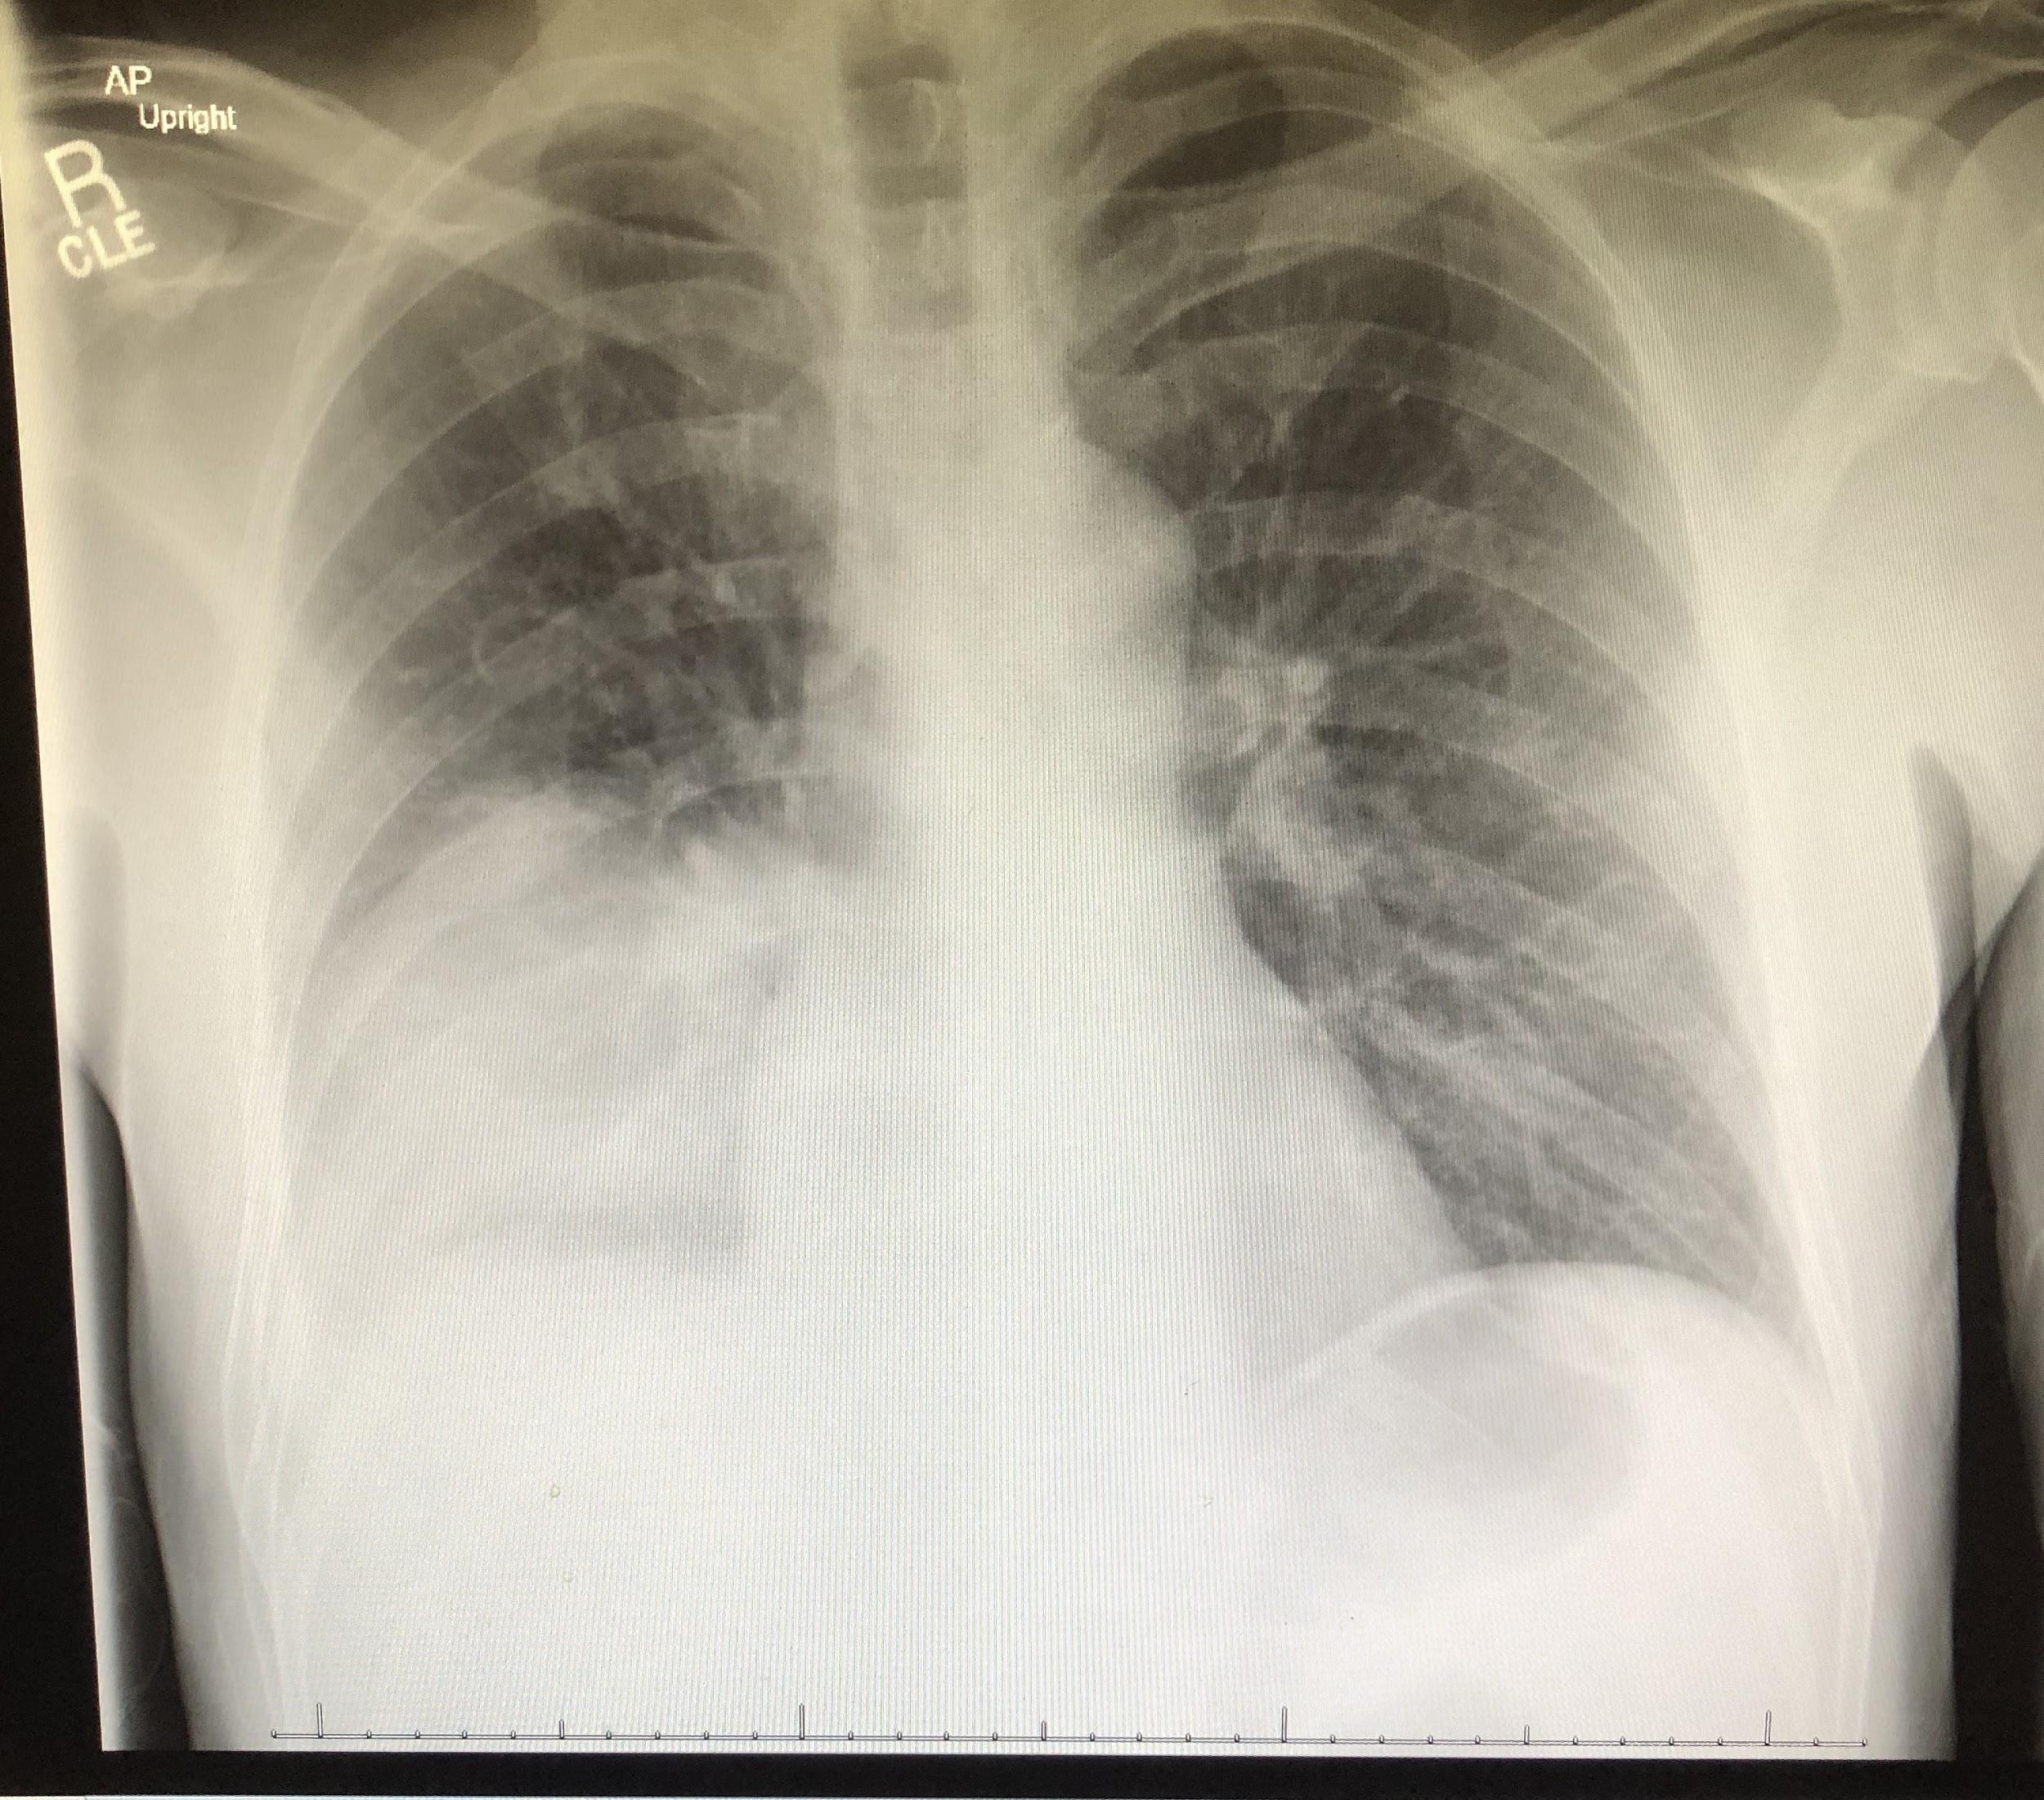

Chest radiographs revealed a dense consolidation in the right lower lobe (Figure 1). Additional imaging included right upper-quadrant ultrasonography, the findings of which were notable for mild intrahepatic dilation and mild biliary sludging. An empiric antibiotic regimen was initiated for community-acquired pneumonia with ceftriaxone, azithromycin, and doxycycline; this regimen subsequently was modified to vancomycin, azithromycin, and cefepime.

Figure 1. Anteroposterior (top) and lateral (bottom) chest radiographs showed an area of focal consolidation in the right middle and lower lung.